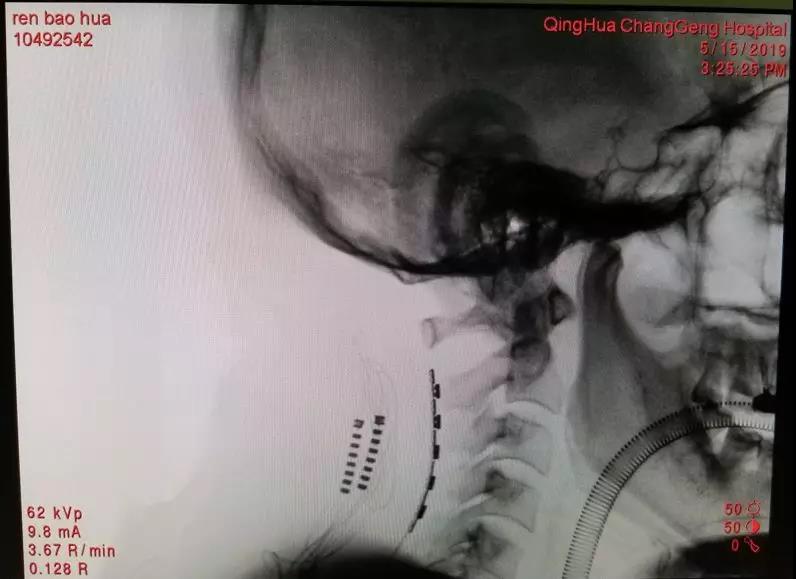

Electrodes accurately implanted in target location

On May 15, 2019, Dr. Jin Wang performed the surgery that implant an electrode sheet in the epidural of the cervical spine, using electrical stimulation to block the conduction of pain signals. There are 16 contacts in 3 rows on the tiny electrode sheet, so that electrical stimulation can be controlled precisely after the surgery. During the surgery, they used intraoperative stimulation combined with neurophysiological monitoring to objectively determine the area of pain that can be covered by electrical stimulation. In the end, they used the O-arm to confirm the precise implantation of the electrode in the cervical epidural space. After stimulation testing for nearly a week after surgery, the patient's left upper limb pain relieved by more than 60%. It was difficult for him to sleep before the surgery because of the pain. But after the surgery, he could sleep for 6 hours per night without medication. In accordance with the clinical trial protocol, Mr. Ren went on to receive implantation of a subcutaneous electrical pulse emitter.

Neurosurgery team used O-arm to confirm the location of the electrode